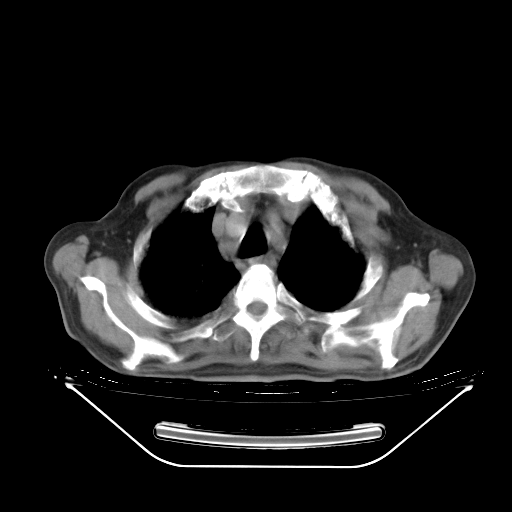

胸腹部CT,诊断意见:左上肺叶钙化灶、左侧胸膜局限性增厚并钙化、胆囊炎。描述部分肺组织呈磨玻璃样改变。